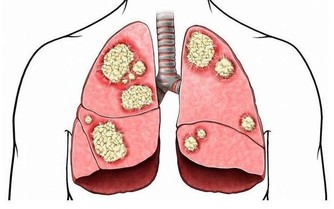

肺臟,左右兩個肺全部切除,呼吸功能完全喪失,2分鐘左右體內氧被耗盡,因為呼吸停止先於心跳,並先於大腦,所以等到全腦死亡後(大約一個小時),人徹底死亡。